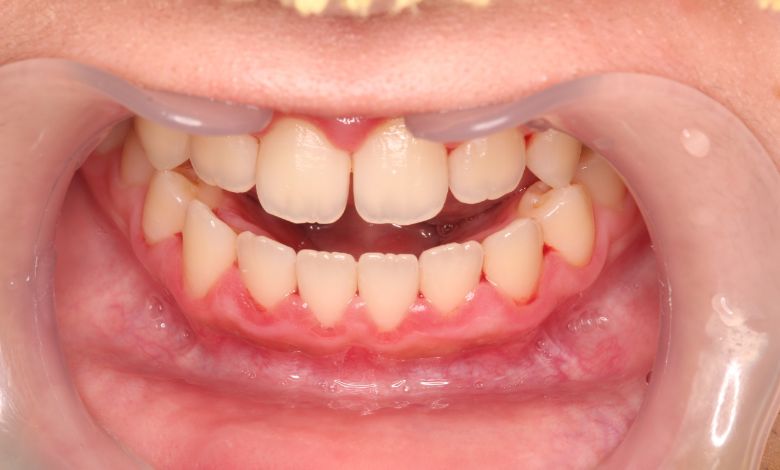

上下顎ともに犬歯が唇側に大きく突出しており、歯列弓が狭小なため、

他院では上下左右4本の便宜抜歯を前提とした矯正治療を提案されていました。

上顎には左右の犬歯が著しく唇側に偏位している

精密検査の結果、当院では抜歯を行わず、歯列弓の拡大によってスペースを確保し、非抜歯での矯正治療を選択しました。歯列の叢生(ガタガタ)は解消され、機能的かつ審美的に優れた咬合が得られました。